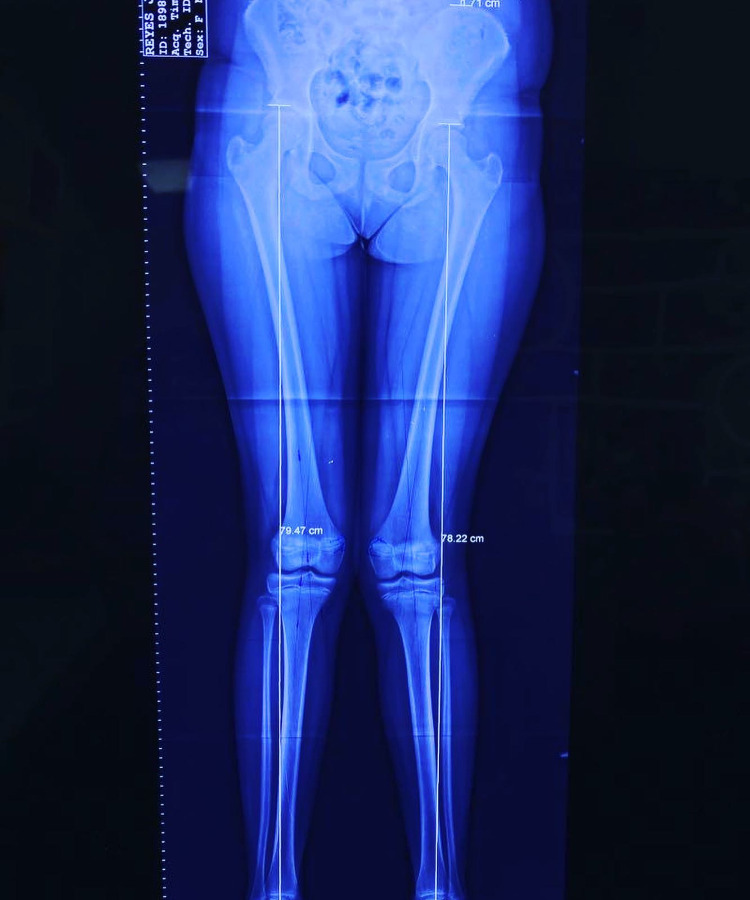

Las deformidades de pie y rodilla incluyen genu varo, genu valgo, pie plano y pie cavo, con causas congénitas o postraumáticas.